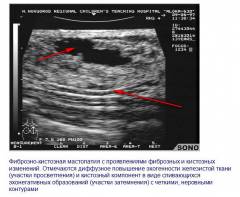

Фиброзно-кистозная мастопатия

Наличие полостей и участков уплотнения.

Фиброзно-кистозная мастопатия характеризуется наличием полостей с жидкостью и участков уплотнения с четкими границами.